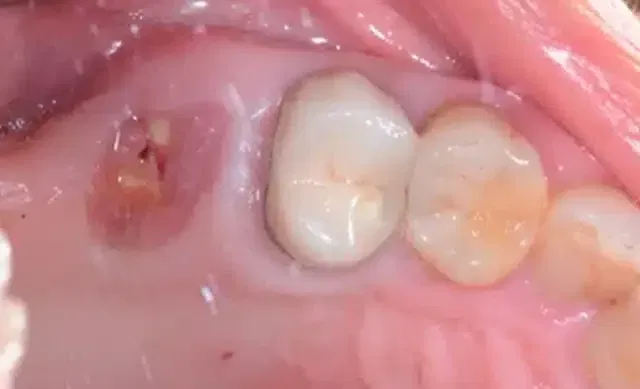

Before delving into the realm of natural remedies, it’s crucial to understand the nature of a cracked tooth and what can and cannot be achieved through natural means. A cracked tooth typically occurs due to a variety of factors, including trauma, teeth grinding (bruxism), and even biting into hard foods. The extent of the crack can range from superficial lines on the enamel to more severe fractures that extend deep into the tooth’s structure.

While natural remedies can help manage the symptoms and promote oral health, they cannot magically mend a severely cracked tooth or replace the need for professional dental care. Cracked teeth require appropriate dental intervention, such as bonding, crowns, or root canals, depending on the severity of the damage.